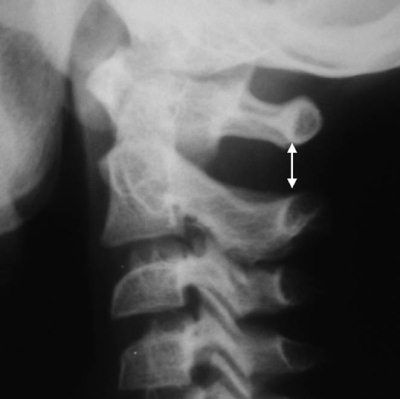

Расширение интерспинального расстояния CI–CII (рис. 4.10)

Расстояние между остистыми отростками – показатель целостности связочного аппарата в шее, и в норме не должно отличаться более чем в 1,5 раза в сегменте выше или ниже исследуемого [5, 6, 7]. У детей это расстояние может резко увеличиваться между CI–CII, что является обычной рентгенологической находкой в норме [5, 7].